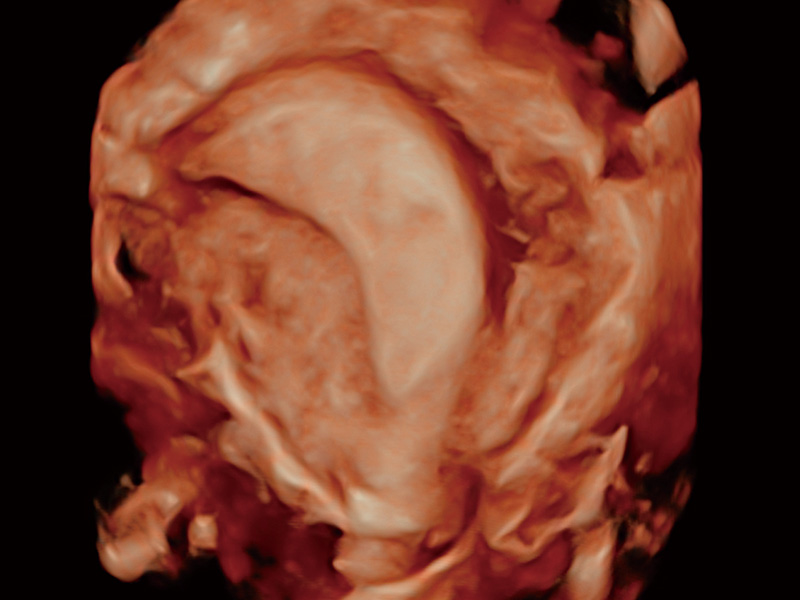

超声引导下胚胎移植

单角子宫